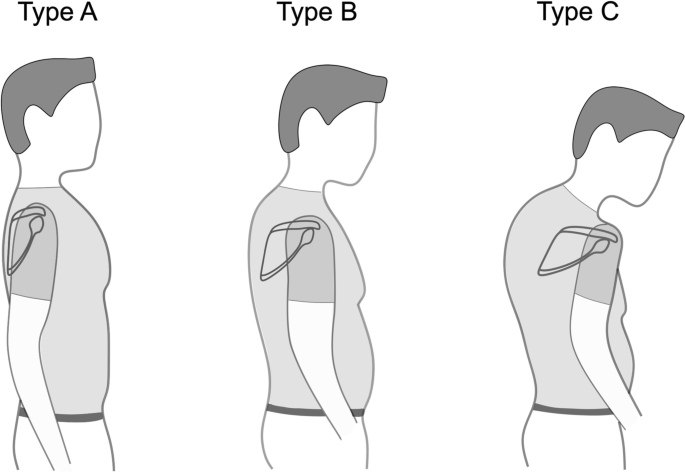

Impaired internal and external rotation pose a challenge in reverse total shoulder arthroplasty (RTSA) [1,2,3,4,5]. The position of the scapula relative to the torso is defined by three motions: scapula internal/external rotation, anterior/posterior tilt and upward/downward rotation, as well as combined forms with translational changes like protraction [6]. Scapulothoracic orientation has been shown to be an important factor influencing simulated range of motion (ROM) in RTSA [2]. A CT-based study showed that with increasing thoracic kyphosis the scapula protracts, internally rotates and anteriorly tilts relative to the body axes [7]. Based on these findings, a classification of shoulder arthroplasty patients into different posture types has been suggested. Patients are categorized from Type A with upright posture and retracted scapulae over average Type B to Type C with kyphotic posture with protracted and internally rotated scapulae [7] (Fig. 1). Moroder et al. further investigated the impact of those static scapula orientation changes on ROM in RTSA, using a modified arthroplasty planning software that accounts for scapulothoracic orientation [2]. In RTSA the humeral component rotates in semicircular movements around the glenosphere. Since scapular internal rotation (SIR) dictates the orientation of the latter implanted glenosphere it was found to play a major role affecting simulated ROM, especially rotational movement [2, 7].

Illustration of three different posture types. From Type A over B to C patients show increasing scapular internal rotation, anterior tilt, protraction, and drooping as well as kyphosis and a barrel-shaped chest according to Moroder et al. [7]

Each shoulder (n = 100) was categorized into three different posture types (Fig. 1) for further subgroup analysis (Type A—upright posture, retracted scapulae; Type B—intermediate; Type C—kyphotic posture with protracted scapulae), based on the 3D measured SIR, as previously described [7]. The following threshold values were used: Type A ≤ 36°, Type B > 36° to 46°, and Type C ≥ 47° [2, 7]. Since each shoulder was evaluated separately, a patient could be categorized as two different types (e.g., 46° left would be Type B and 47° right would be Type C).